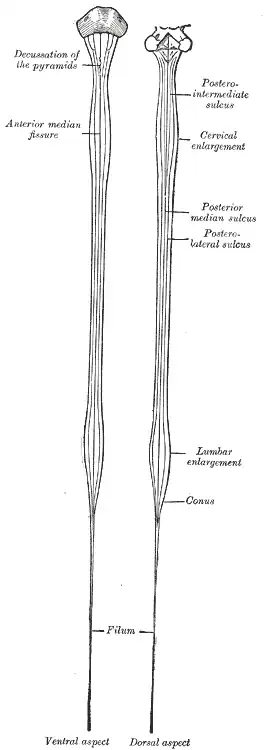

The spinal cord is the main pathway for information connecting the brain and peripheral nervous system.[3][4] Much shorter than its protecting spinal column, the human spinal cord originates in the brainstem, passes through the foramen magnum, and continues through to the conus medullaris near the second lumbar vertebra before terminating in a fibrous extension known as the filum terminale.

The human spinal cord is an estimated 45 centimetres (18 inches) long in average-height males and about 43 cm (17 in) in average-height females. It is ovoid-shaped and is enlarged in the cervical and lumbar regions. The cervical enlargement, stretching from the C4 to T1 vertebrae, is where sensory input comes from and motor output goes to the arms and trunk. The lumbar enlargement, located between T10 and L1, handles sensory input and motor output coming from and going to the legs.

The spinal cord is elliptical in cross section, being compressed dorsolaterally. Two prominent grooves, or sulci, run along its length. The posterior median sulcus is the groove in the dorsal side, and the anterior median fissure is the groove in the ventral side.

The spinal cord proper terminates in a region called the conus medullaris, while the pia mater continues as an extension called the filum terminale, which anchors the spinal cord to the coccyx. The cauda equina ("horse's tail") is a collection of nerves inferior to the conus medullaris that continue to travel through the vertebral column to the coccyx. The cauda equina forms because the spinal cord stops growing in length at about age four, even though the vertebral column continues to lengthen until adulthood. This results in sacral spinal nerves originating in the upper lumbar region. For that reason, the spinal cord occupies only two-thirds of the vertebral canal. The inferior part of the vertebral canal is filled with cerebrospinal fluid and the space is called the lumbar cistern.[8]

Enlargements

There are two regions where the spinal cord enlarges:

- Cervical enlargement – corresponds roughly to the brachial plexus nerves, which innervate the upper limb. It includes spinal cord segments from about C4 to T1. The vertebral levels of the enlargement are roughly the same (C4 to T1).

- Lumbar enlargement – corresponds to the lumbosacral plexus nerves, which innervate the lower limb. It comprises the spinal cord segments from L2 to S3 and is found about the vertebral levels of T9 to T12.

A longer view of the spinal cord

A longer view of the spinal cord -